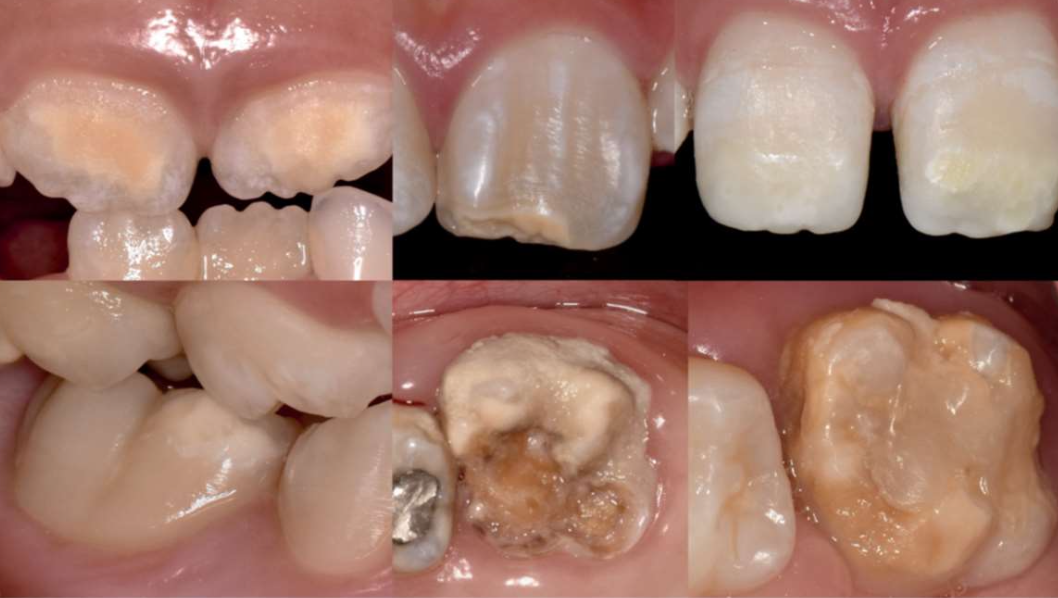

Xerostomia (dry mouth,口乾症) | - | 舌乳頭萎縮、鵝口瘡(oral candidiasis), 蛀牙 ![]() |